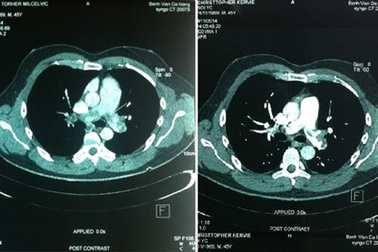

Cứu du khách người Australia tắc động mạch phổi cấp nguy kịchCác bác sĩ khoa Hồi sức tích cực, BV Đà Nẵng đã cứu sống một bệnh nhân ngoại quốc C.McKervie bị tắc động mạch phổi cấp nhờ thuốc tiêu sợi huyết.